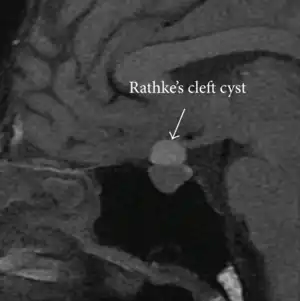

| Rathke's cleft cyst in a 53-year-old man with a pituitary adenoma and acromegaly |

A Rathke's cleft cyst is a benign growth on the pituitary gland in the brain, specifically a mucin-filled[1] cyst in the posterior portion of the anterior pituitary gland.[2][3] It occurs when the Rathke's pouch does not develop properly and ranges in size from 2 to 40 mm in diameter.[3]